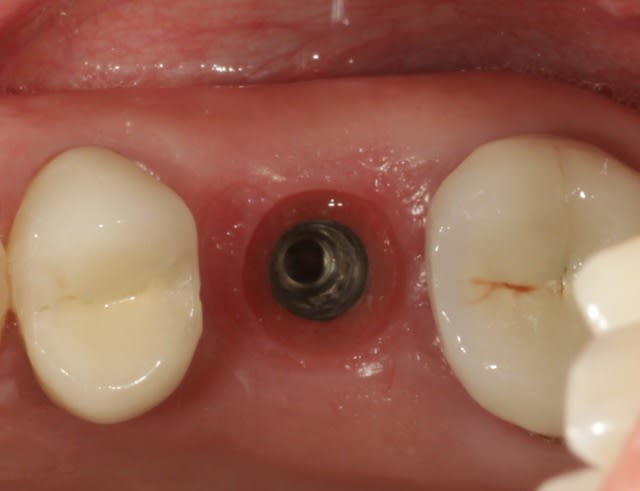

ok je vais essayer de répondre à tout le monde,

y a t il des études avec des alvéoles d'extraction comblées au Bio-Oss sans membrane? oui y en a plein, depuis une quinzaine d'années, là j'ai pas le temps de vous faire une revue de littérature, ni ce week end mais si ça vous intéresse on peut faire ça lundi.

est ce qu'on va avoir tout le Bio-Oss transformé en os? clairement la réponse est non,

est ce que cela aurais été mieux de mettre une membrane? pour avoir de l'os sans doute, mais alors il aurait fallu recouvrir cette membrane par un greffon conjonctif ou épithélio-conjonctif et là plus de vis de cicatrisation, enfin c'est plus la même procédure, pour un gain qui est pas évident.

est ce que je veux avoir de l'os? franchement on s'en fout l'objectif c'est surtout de maintenir le volume, l'implant est dans le septum il est quasiment entouré d'os partout, donc peu importe.

voilà j'espère avoir répondu à vos questions.